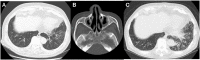

A 75-year-old man presented to our hospital with chronic sinusitis, bronchiectasis, and chronic lower respiratory tract infections. He began taking erythromycin in August, X-2. The chronic lower respiratory tract infection gradually worsened, and clarithromycin was started on May 11, X. He became aware of fever and numbness in his lower legs on June 4, X. The sign occurred soon after oral clarithromycin and blood tests showed an elevated eosinophil count and C-reactive protein (CRP) levels, positive MPO-ANCA antibodies, and positive for drug-induced lymphocyte stimulation test (DLST); we diagnosed eosinophilic granulomatosis with polyangiitis (EGPA) associated with clarithromycin administration.